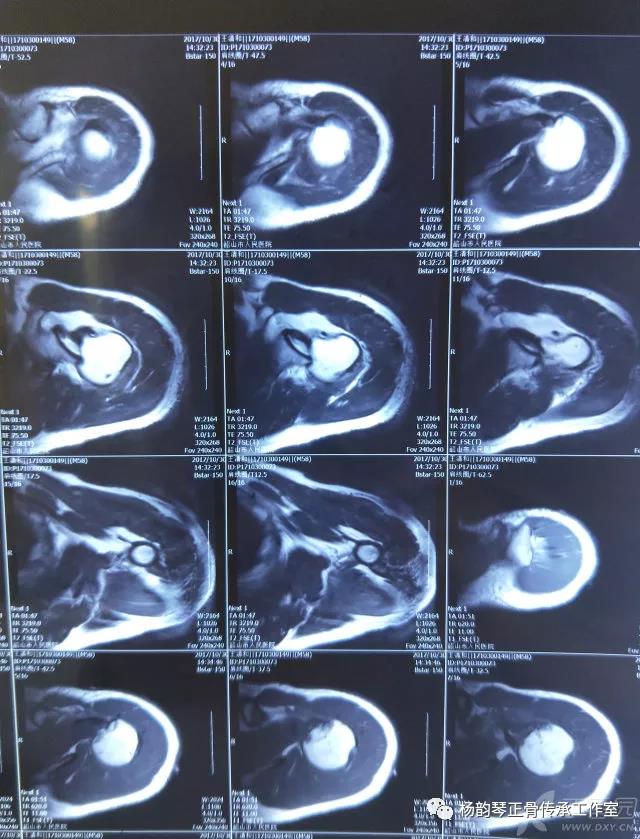

磁共振检查也完善了,还是报了个肩关节半脱位……影像科已经把坑挖好了……

接诊医生直接跳坑里了